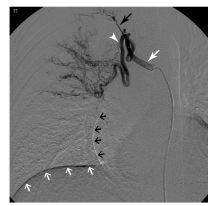

L’artériographie est réalisée uniquement à visée thérapeutique (embolisation) (figure 92.4).

Fig. 92.4. Artériographie bronchique, cliché soustrait de face (même patient qu’en figure 97.2).

Dilatation importante d’un tronc inter-costo-bronchique droit (flèche blanche) et de l’artère bronchique qui en provient (tête de flèche) avec un territoire d’aval pathologique. Flèche noire : artère intercostale ; flèches blanches : coupole droite du diaphragme ; flèches noires : bord de l’atrium droit.

Source : CERF, CNEBMN, 2022.